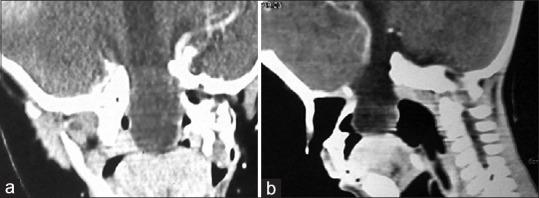

Trans -sellar trans-sphenoidal encephalocele is an extremely rare entity. We present the case of an 18-month old boy who presented with a trans-sellar, trans-sphenoidal encephalocele associated with cleft lip, cleft palate and microphthalmia. This patient was treated successfully by a trans-cranial extra-dural route. In this paper, we discuss the clinico-radiological findings as well as various surgical options in managing these rare lesions and briefly review the literature.

经蝶鞍经蝶骨脑膨出是一种极为罕见的病症。我们报告一例18个月大的男孩,其患有经蝶鞍、经蝶骨脑膨出,并伴有唇裂、腭裂和小眼症。该患者通过经颅硬膜外途径成功治愈。在本文中,我们讨论了这些罕见病变的临床放射学表现以及各种手术治疗方案,并简要回顾了相关文献。